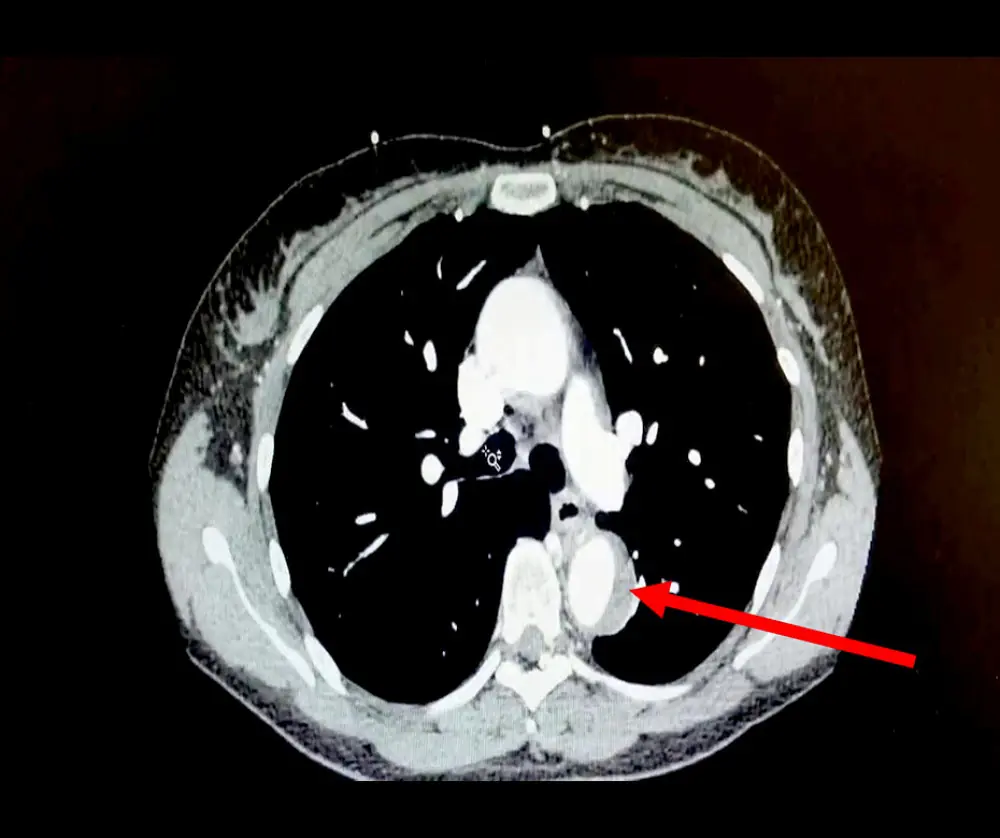

When the woman was examined at the hospital, medical staff discovered that she experienced a form of acute aortic syndrome (AAS) - a potentially life-threatening condition.

Doctors found a leak in her aorta - a large artery that carries blood through the body. The condition is very scary, as for every hour a patient has not been treated, their odds of death rise by one percent.